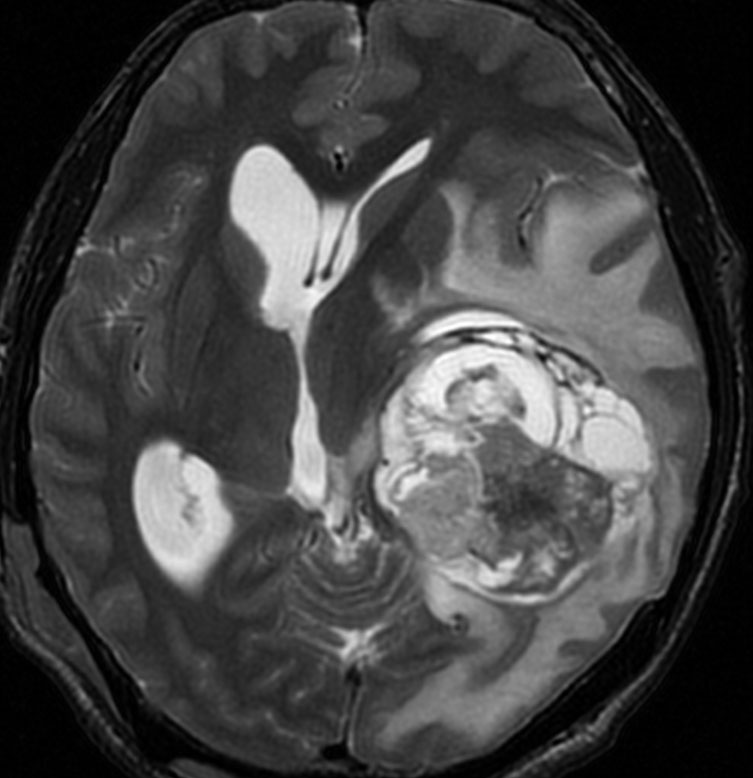

高齢者の無症候例です

60代の女性に無症候で発見された稀な部位のPXA。結節様ですが脳とのはっきりした境はなく,多房性ののう胞を伴っていました。T2とFLAIR像ではわずかな浸潤像あるいは腫瘍周辺浮腫が疑われます。PXAに特徴的な画像ですが,大脳深部発生でもあり,PXAと画像診断することはできません。定位脳生検術 MRI-guided sterotactic biopsyで病理組織診断を行ない経過観察しました。

3年観察したら嚢胞を伴って増大しました。幸いのう胞性拡大が脳表方向であったのでparietal transcortical approachで全摘出できました。側脳室三角部腫瘍への到達法と同じアプローチですが,この経路では頭頂葉症候を後遺することがありません。

術後は無症状で8年間再発はありません。